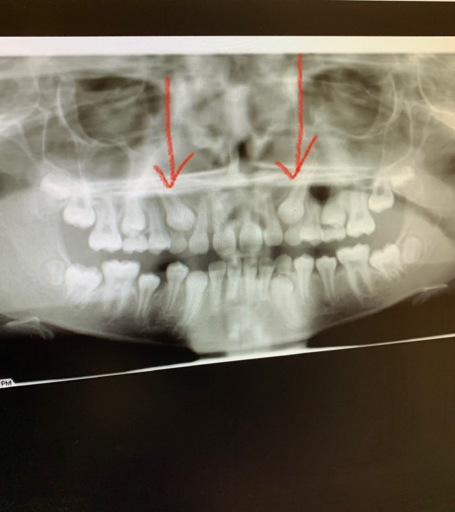

You need to seek the advice of a dental professional, preferably a periodontist or oral surgeon, who does this kind of work, and have him or her take an X-ray, either a CT scan or Panorex. The image should be not only of your teeth but also your jawbone. This will allow you to rule out any kind of infection, cyst, or problem at the extraction site that could account for the recurring swelling. It's possible that there's a problem with the tooth adjacent to the extraction socket. The tooth might have a cavity or need a root canal treatment, which would makes it feel as though it's affecting the socket area.

Why Am I Missing Roots on My Wisdom Teeth?

I'm having my wisdom teeth taken out soon. I was told that none of the four wisdom teeth have roots. I even saw the x rays, and it just looked like the top of a normal molar. They have not broken through the gums yet, but they felt I needed them out...